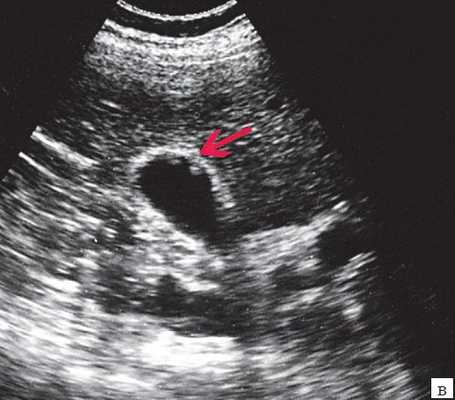

Специальную сверхтонкую струну-проводник удалось провести в сегментарный проток правой доли печени (рис. 2), после чего принято решение первоочередно расширить просвет протока специальными эндоскопическими бужами (рис. 3, 4), постепенно увеличивая диаметр последних.

Когда необходимый диаметр был достигнут, выполнено стентирование левого долевого желчного протока печени (рис. 5).